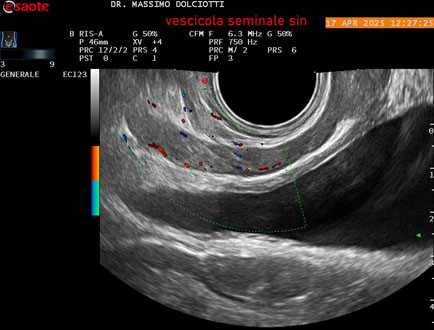

Ecografia del: 17/04/2025

Sonda: Convex Multifrequenza 1-8 MHz, Endocavitaria Multifrequenza 3-9 MHz e 3-13 MHz

Età Paziente: M 35 anni

Motivazione dell'esame: disuria.

Commento all'esame: le immagini ed il video documentano la prostata di ecostruttura regolare e morfovolumetria normale con diametro trasversale di 40 mm, diametro anteroposteriore di 21 mm e diametro longitudinale di 43 mm, con volume prostatico calcolato di 18 cc (v.n. < 20 cc), il profilo prostatico è regolare e netto, non si documentano calcificazioni intraghiandolari, la vascolarizzazione della ghiandola è normale. La vescicola seminale destra presenta diametro longitudinale di 44,4 x 7,8 mm, la vescicale seminale sinistra ha diametro longitudinale di 45,3 mm x 7,2 mm.

Conclusioni: prostata normale (normal prostate).